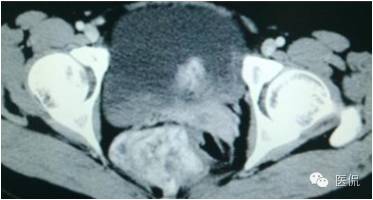

病史

女,37岁,体检超声发现盆腔包块一周。无其他异常。

CT平扫(CT值23HU)

增强动脉期(CT值31HU)

增强静脉期(CT值62HU)

增强延迟期(CT值106HU)

结果

手术是:盆腔占位,病理为:血管肌纤维母细胞瘤。与肛门粘连,于是同时做了肛门的处理。